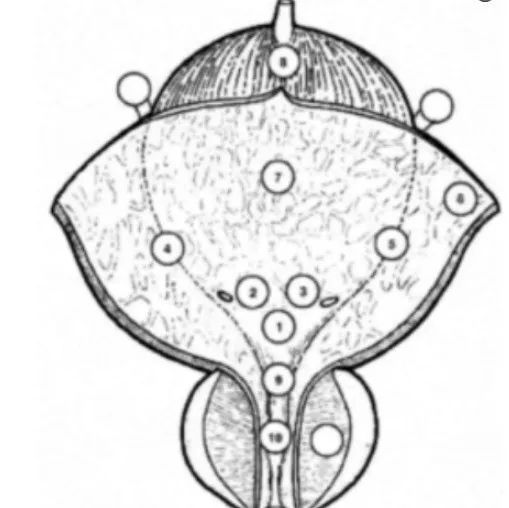

膀胱活检:在选择有代表性的膀胱粘膜的映射点时,活检部位应包括膀胱三角区、顶部、右侧及左侧壁、前壁及后壁。有条件时,光动力学诊断(Photodynamic diagnosis,PDD)是一种靶向导引活检部位的实用方法。